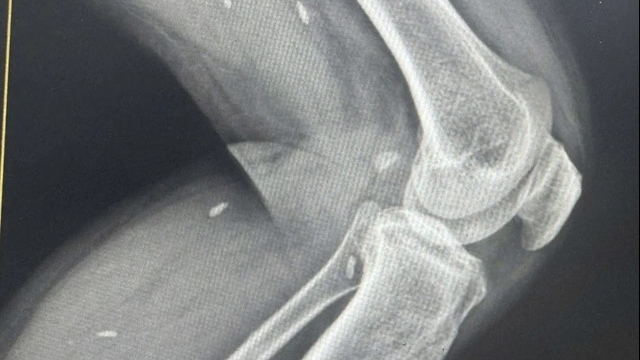

Trường điện từ có thể gây ung thư não.